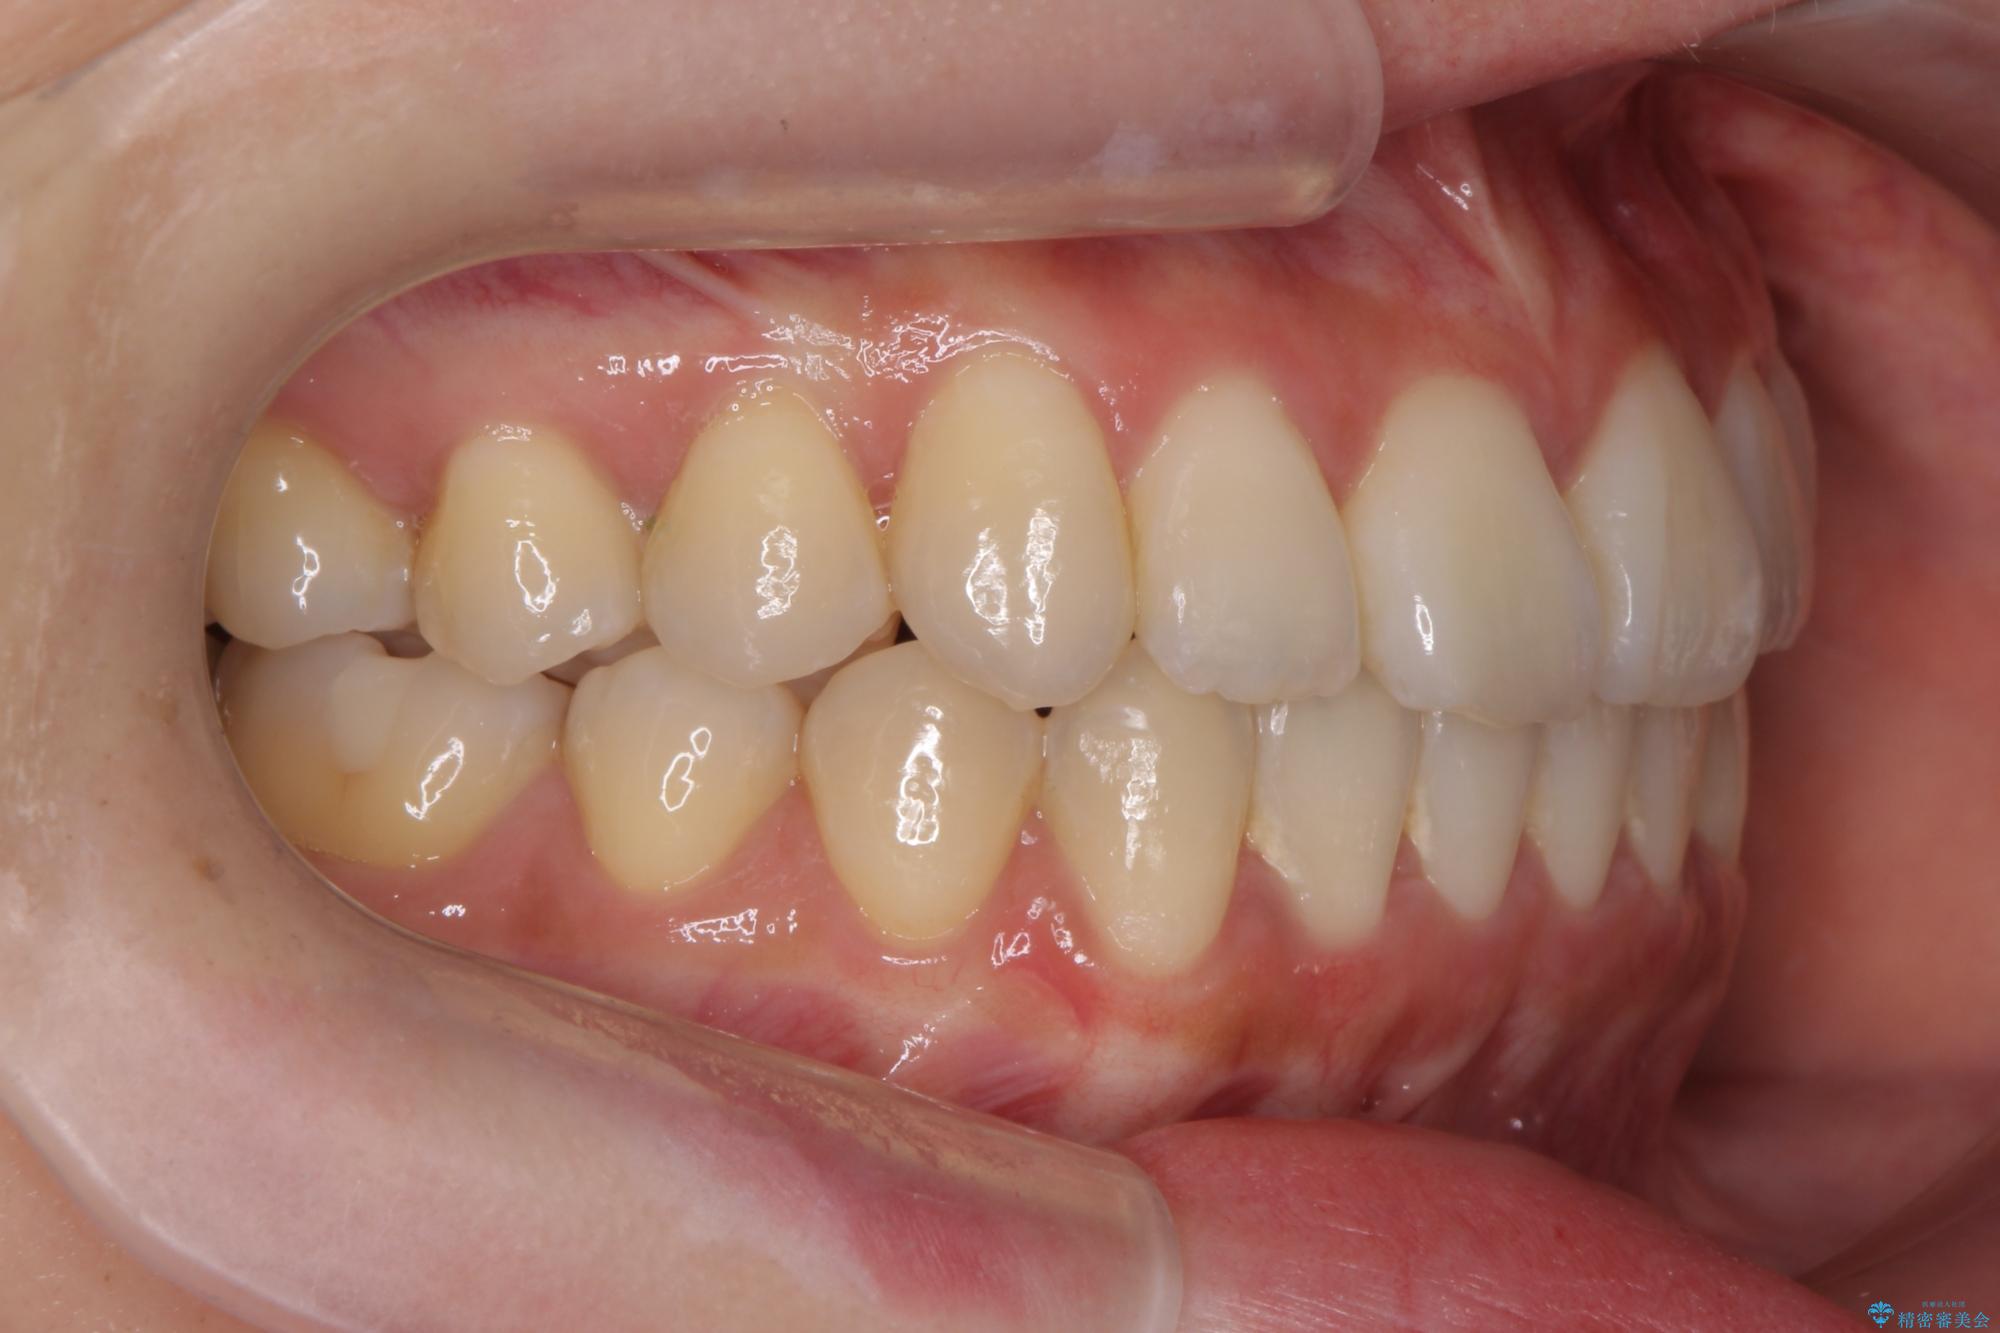

前歯のねじれが気になる、歯並びを改善したいとご来院された患者様です。

歯のねじれをきれいに取るのは、インビザライン(マウスピース矯正)だけでは難しい動きです。そのため、事前に4か月間の部分ワイヤー矯正を行い、治療期間を短くし、より美しい仕上がりを目指す計画です。

前歯が綺麗に並び、大変ご満足いただけました。